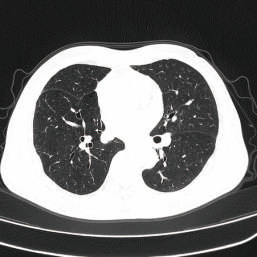

When performing CT scan examination for a patient injured in a car accident, doctors can obtain images of full body in five to ten minutes. These images can help them immediately identify life-threatening injuries such as cerebral hemorrhage, pulmonary contusions, and lacerations of the internal organ, which is vital for doctors to implement target treatment (e.g., blood pressure control, respiratory function maintenance, emergency hemostasis).

Traumatic injuries can be deeply deceptive: life-threatening damage can hide beneath a seemingly normal surface. Thus, these injuries demand exceptional diagnostic precision — even a minor mistake can mess up the treatment plan. This is where the CT scanner proves indispensable. Using millimeter-level imaging, it performs a virtual “dissection” of the body, building a detailed picture layer by layer, from the skin inward. Beyond simply detecting injuries, it locates them with accuracy, gauges their severity, and characterizes their nature — leaving no hidden threat overlooked.